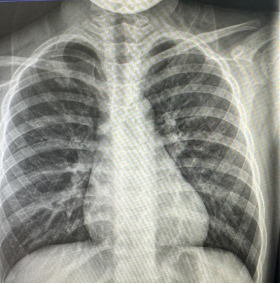

朱某,男,2016-3-15出生,因“跌倒致左肩疼痛伴活動受限2小時”2019年12月12日來我院門診。檢查發現左鎖骨區見腫脹、畸形,明顯壓痛,左肩活動受限。本院X線攝片示:左鎖骨骨折,斷端明顯重疊移位(圖1),予以8字繃帶外固定制動,定期隨訪。2020年1月17日復診述左肩無腫痛,活動基本正常,攝片示:左鎖骨骨折,斷端對線欠佳,局部明顯骨痂形成(圖2)。2020年6月8日再次復查攝片示:左鎖骨骨折,斷端對線可,已骨性愈合(圖3)。2023年9月26日再復查攝片示:左鎖骨骨折部位已完成塑形,與健側無明顯差異(圖4)。

圖3